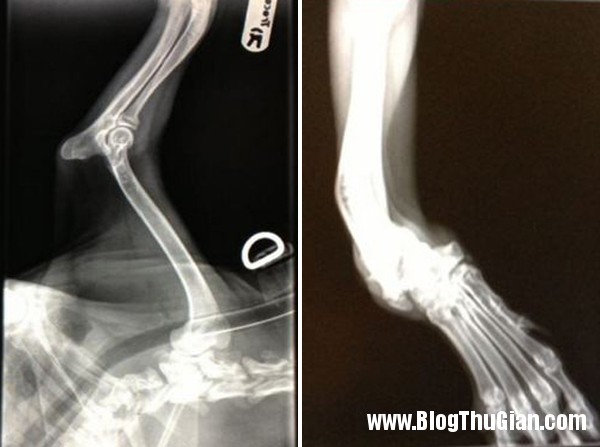

Hình chụp X-quang đôi chân dị tật của Sandy

Các bác sĩ cho rằng dị tật của đôi chân là hậu quả của suy dinh dưỡng. Do thiếu ăn nên đôi chân củaSandy đã phát triển ngày một lệch lạc và cong vênh.